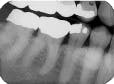

Overlap of contact surfaces

Perhaps the most common error is the overlapping of contacting surfaces (see Radiograph 1). When this occurs, the interpretation of caries is difficult at best. At worst, depending on the degree of overlap, interpretation often becomes virtually impossible.

The overlap is the result of incorrect horizontal angulation. With the paralleling technique, improper film-holder placement can be the cause. A simple adjustment in the film-holder`s position places it parallel to the facial surfaces of the teeth being exposed.

But the overlap can also be the result of errors in the angle of projection either mesiodistally or distomesially. When the horizontal plane projection is directed from mesial to distal, the resulting larger areas of overlap appear in the posterior portion of the film. Conversely, if the larger overlap appears in the anterior portion of the film, the horizontal plane of projection was directed distal to mesial.

To change this, place the film parallel to an imaginary line that is parallel to the facial surfaces of the teeth. The plane of the positioning indicating device/cone (PID) should then be parallel to this line and the film together. To determine the degree of overlap, use this general rule: If the overlap covers more than one-half of the enamel`s width, the degree of incipient decay and etchings are difficult to determine, and major technique problems need to be addressed.